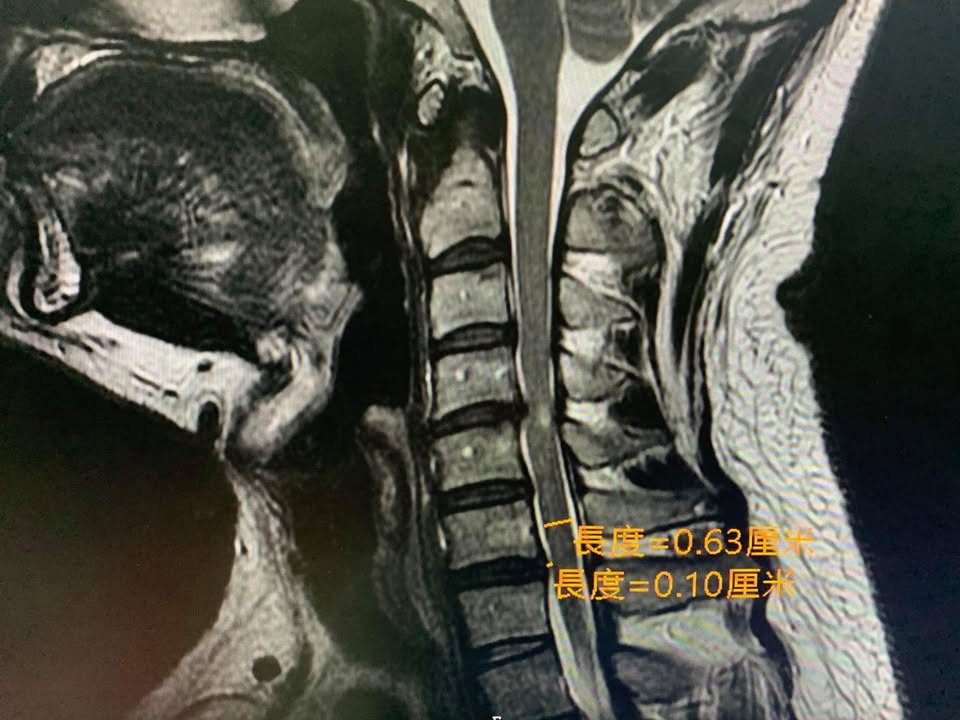

#核磁共振證實C4C5突出壓迫

後來在今年去某醫學中心拍攝頸椎核磁共振證實頸椎第五神經根卡壓,因為傳統復健超過三個月仍然沒重大改善,頸椎酸痛到上臂都非常不舒服,經過友人介紹於今年9月底來接受治療

❇️診斷:C4C5椎間盤突出壓迫神經根與硬膜囊